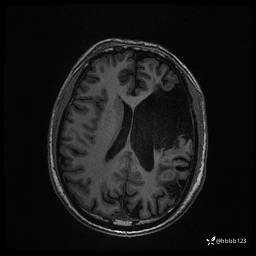

患者男,43岁。

简要病史:癫痫患者复诊,昨日发作5-6次,建议住院进一步治疗。

入院完善脑癫痫组合序列:

T2 Flair: